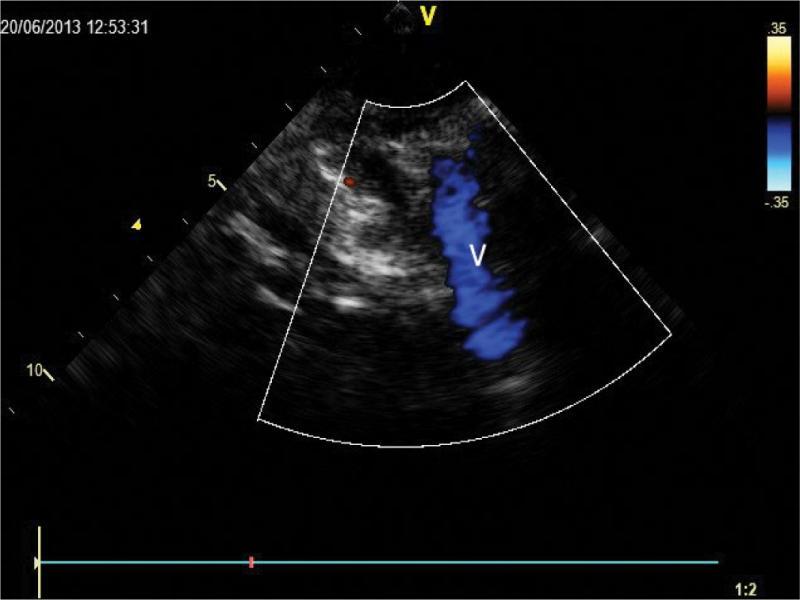

Corresponding view during diastole, with flow noted only in the venous vessel (V) adjacent to the aorta